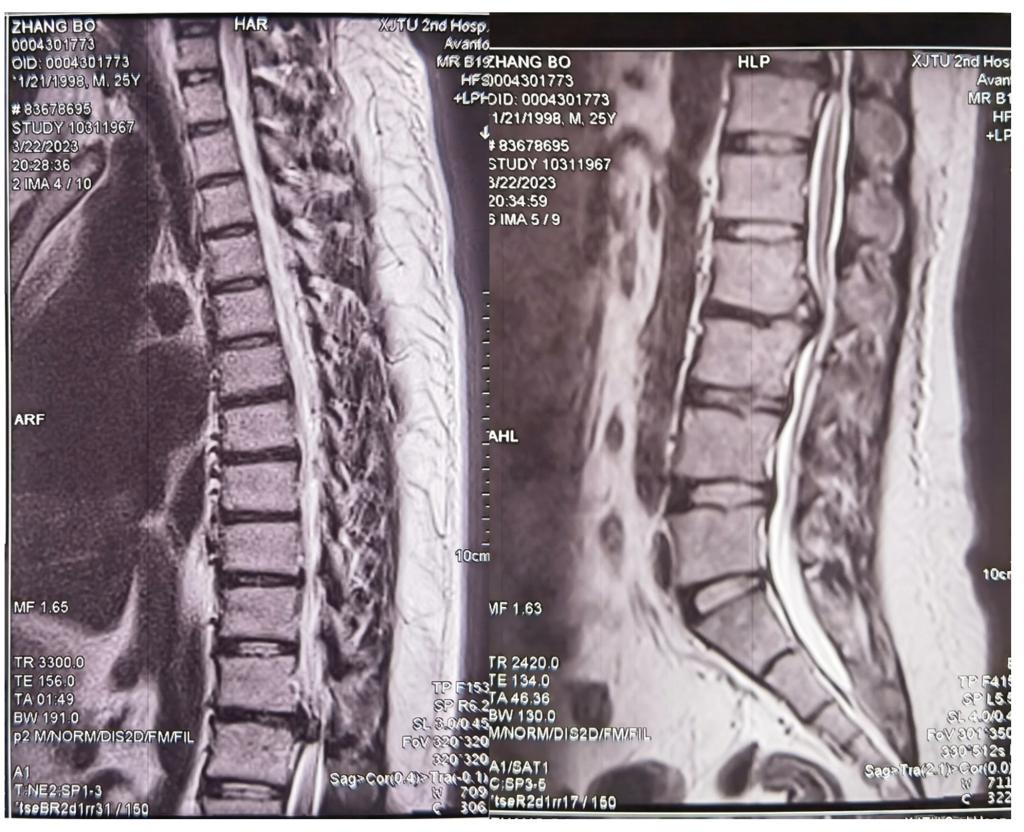

患者为一25岁小伙子,5月前无明显诱因出现右下肢麻木,伴有腰痛和右下肢无力,在当地医院诊断为“腰椎间盘突出”并给予微创介入治疗,但效果不佳。剧烈的疼痛和下肢的无力感使他辗转反侧,夜不能眠,不得已之下又二次进行微创胶原酶注射治疗,这次手术下来症状更加重了,走路不稳,摇摇晃晃,而且疼痛没有任何减轻。这次在多方打听之下,选择了交大二院脊柱外科。

李锋涛副主任医师在接诊患者后,立即对患者进行了详细的查体,发现患者不仅存在上述症状,腹股沟区及股前区都有感觉减退的表现,觉得不仅仅是腰椎间盘突出症的表现,针对性进行胸椎排查,发现患者还存在严重的胸椎椎管狭窄表现。详查文献后,发现这是一例相对少见的跳跃性(非连续)多节段胸腰椎椎间盘退变 (“skipped” level nonconsecutivedisc degeneration, SLDD)疾病。

下一步的治疗策略令有着丰富脊柱手术经验的李浩鹏主任和李锋涛教授团队犯了难:胸椎椎管严重狭窄,前方的椎间盘及后方韧带前后夹击,椎管的侵占率达到了90%以上,手术操作稍有不慎非死即瘫;腰椎经过之前两次手术治疗,局部解剖结构早已变得面目全非,而且胶原酶注射后局部瘢痕黏连严重,神经损伤风险陡然提升。面对着年轻小伙子的殷切期待,李浩鹏主任最终决定运用智能化的手段,在导航机器人的辅助下,采用直观定位技术进行置钉减压,使手术更精准、更便捷、更安全。